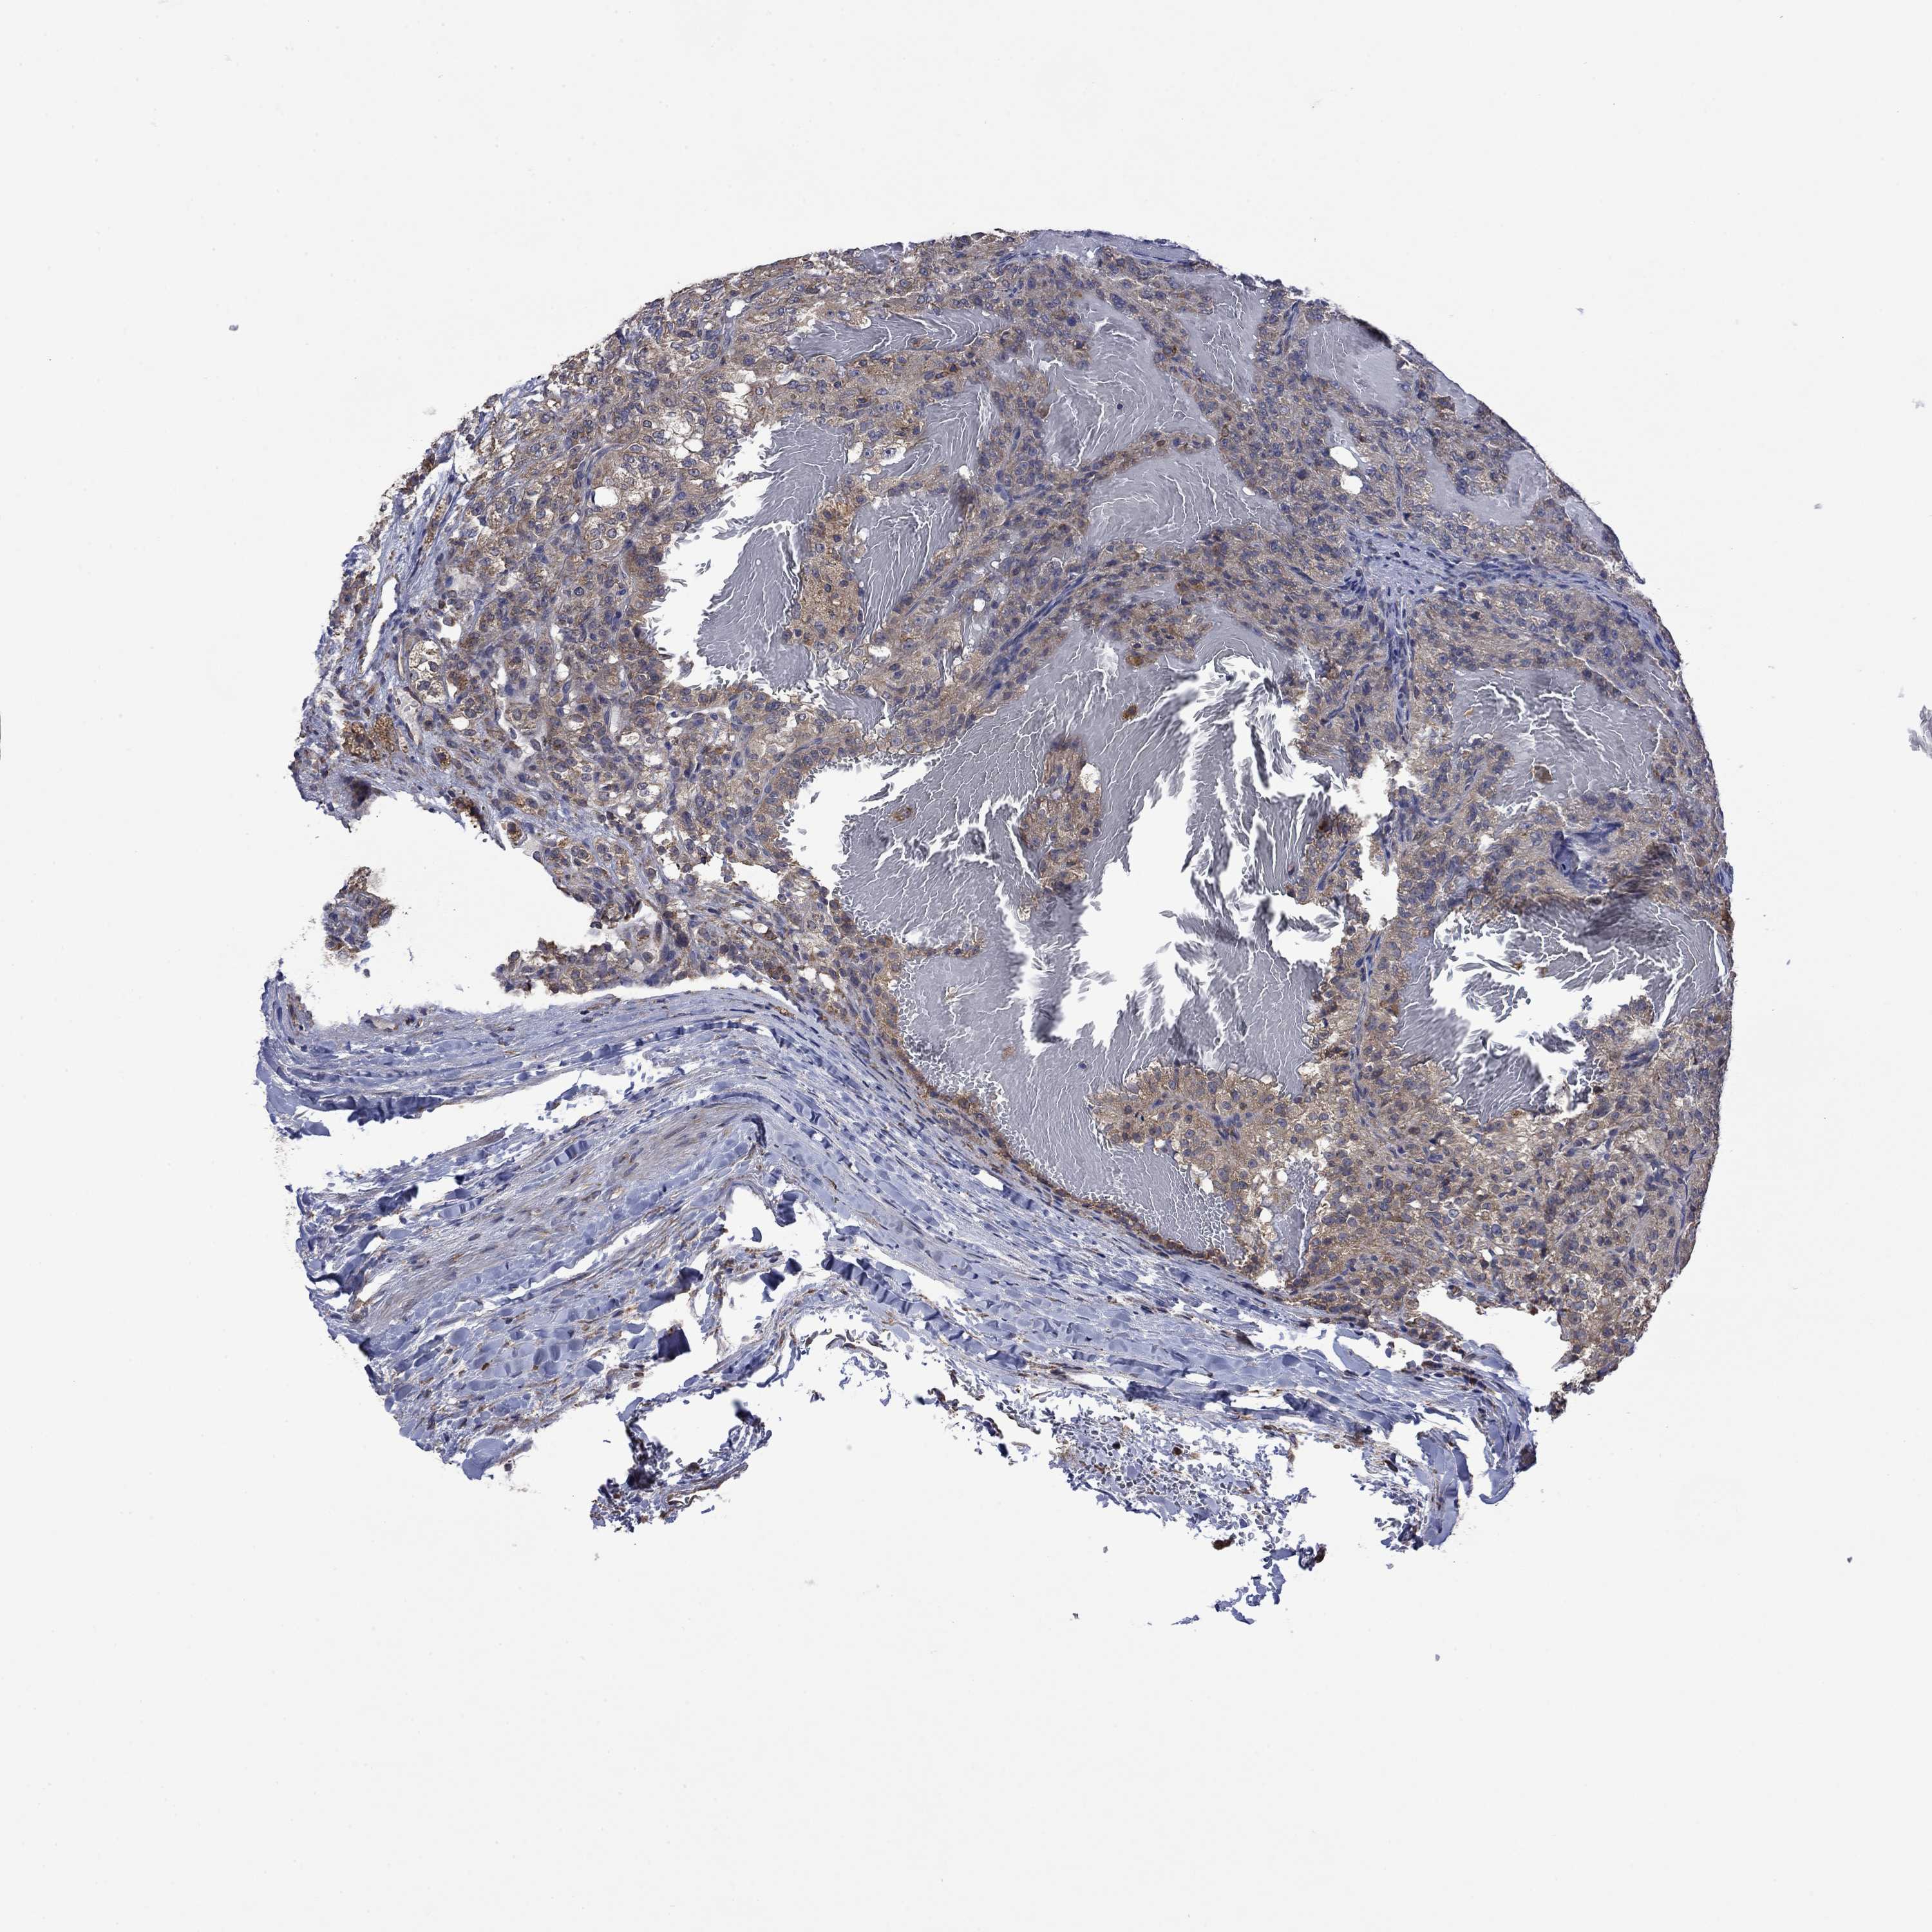

KIDNEY RENAL PAPILLARY CELL CARCINOMA (TCGA) - Interactive survival scatter ploti

The Survival Scatter plot shows the clinical status (i.e. dead or alive) for all individuals in the patient cohort, based on the same data that underlies the corresponding Kaplan-Meier plots. Patients that are alive at last time for follow-up are shown in blue and patients who have died during the study are shown in red.

The x-axis shows the expression levels (FPKM) of the investigated gene in the tumor tissue at the time of diagnosis. The y-axis shows the follow-up time after diagnosis (years). Both axes are complimented with kernel density curves demonstrating the data density over the axes. The top density plot shows the expression levels (FPKM) distribution among dead (red) and alive patients (blue). The right density plot shows the data density of the survived years of dead patients with high and low expression levels respectively, stratified using the cutoff indicated by the vertical dashed line through the Survival Scatter plot. This cutoff is automatically defined based on the FPKM cutoff that minimizes the p-score. The cutoff can be changed by dragging the vertical line or by entering a cutoff value in the square labeled "Current cut-off".

Under the Survival Scatter plot the p-score landscape (black curve; left axis) is shown together with dead median separation (red curve; right axis). Dead median separation is the difference in median mRNA expression between patients who have died with high and low expression, respectively. It is calculated as follows: median FPKM expression of dead patients with high expression - median FPKM expression of dead patients with low expression. This is intended to aid the user in visually exploring custom cutoffs and the associated p-scores and dead median separation.

Individual patient data is displayed and can be filtered by clicking on one or more of the category buttons on the top of the page. Categories describing expression level and patient information include: high, low, alive, dead, female, male and tumor stages. The scale of the x-axis can be toggled between linear and log-scale by clicking on the "x log" button. Mouse-over function shows TCGA ID, patient information and mRNA expression (FPKM) for each patient.

& Survival analysisi

Kaplan-Meier plots summarize results from analysis of correlation between mRNA expression level and patient survival. Patients were divided based on level of expression into one of the two groups "low" (under cut off) or "high" (over cut off). X-axis shows time for survival (years) and y-axis shows the probability of survival, where 1.0 corresponds to 100 percent.

FURIN is not prognostic in Kidney Renal Papillary Cell Carcinoma (TCGA)